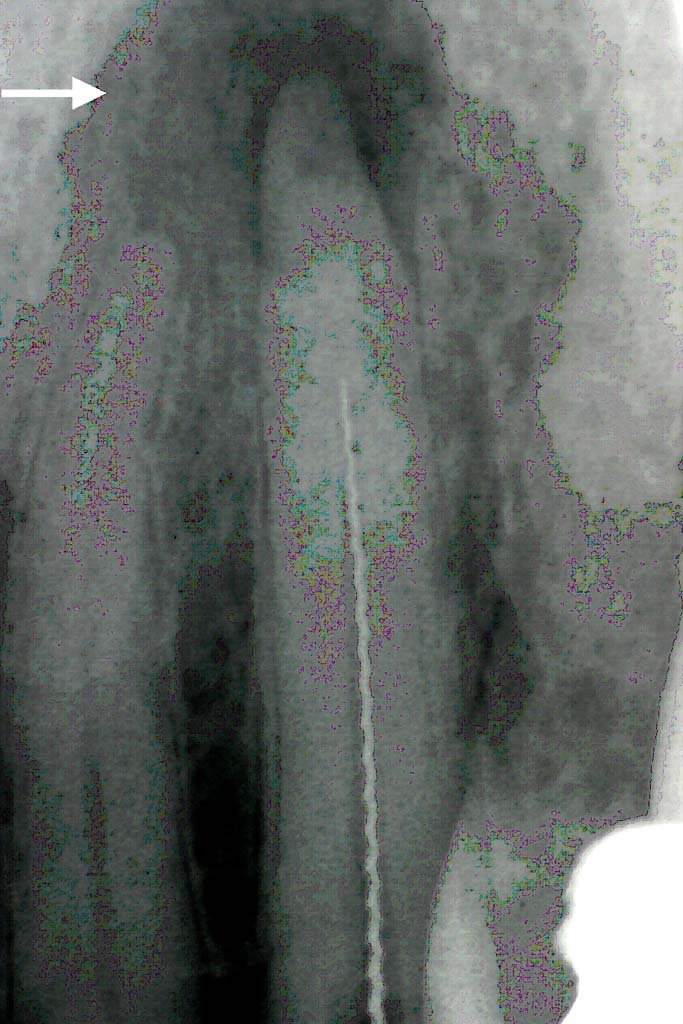

In allen Fällen der Zahnmarksentzündung und insbesondere bei Entzündungen der Wurzelspitze empfiehlt sich neben der herkömmlichen chemisch-mechanische Aufbereitung des Wurzelkanals die zusätzliche Laserung der Wurzelkanalinnenseiten. Dazu wird eine dünne Glasfaser angewendet, die die Laserenergie in den Wurzelkanal leitet. Mit der Laserenergie wird ein sehr großer Teil der Bakterien (bis 97%) in der Wurzelkanalwandung abgetötet (=Wurzelkanalsterilisation) , der nach der chemisch-mechanischen Aufbereitung noch im Kanal und in der Zahnwurzelwandung verblieben ist.

Zudem bewirkt die Laserenergie einen Verschluß der sogenannten Dentintubuli an den Kanalinnenwänden. Diese Dentintubuli sind feinste Känäle der Wurzelwandung, die ebenso wie der Hauptwurzelkanal mit der Wurzeloberfläche des Zahnes in Verbindung stehen. Der Verschluß dieser Kanälchen durch den Laser verhindert somit eine Besiedelung der Wurzelumgebung mit Bakterien aus dem Wurzelkanal heraus (=hermetischer Verschluß).

Besteht bereits ein Granulom so kann durch die Laserbehandlung in den meisten Fällen auf die sonst notwendige Wurzelspitzenresektion verzichtet werden. Der Organismus ist nach der vorbeschriebenen Laserbehandlung zumeist in der Lage, das Granulom an der Wurzelspitze wieder aufzulösen. Die Regeneration des Kieferkochens an der Wurzelspitze muss 4-6 Monate nach der laserunterstützten Wurzelkanalbehandlung durch eine erneute Röntgenaufnahme kontrolliert werden.

Der unterstützende Lasereinsatz bewirkt somit ein Höchstmaß an Keimreduktion im Wurzelkanal und einen optimierten Verschluß zur Zahnumgebung. Selbst stark infizierte Zähne können dadurch zur Ruhe kommen, die mit herkömmlichen Mitteln nicht hätten erhalten werden können. Dies haben Untersuchungen von Prof. Gutknecht am Klinikum der RWTH Aachen eindeutig belegt.

Behandlungsbeispiel: